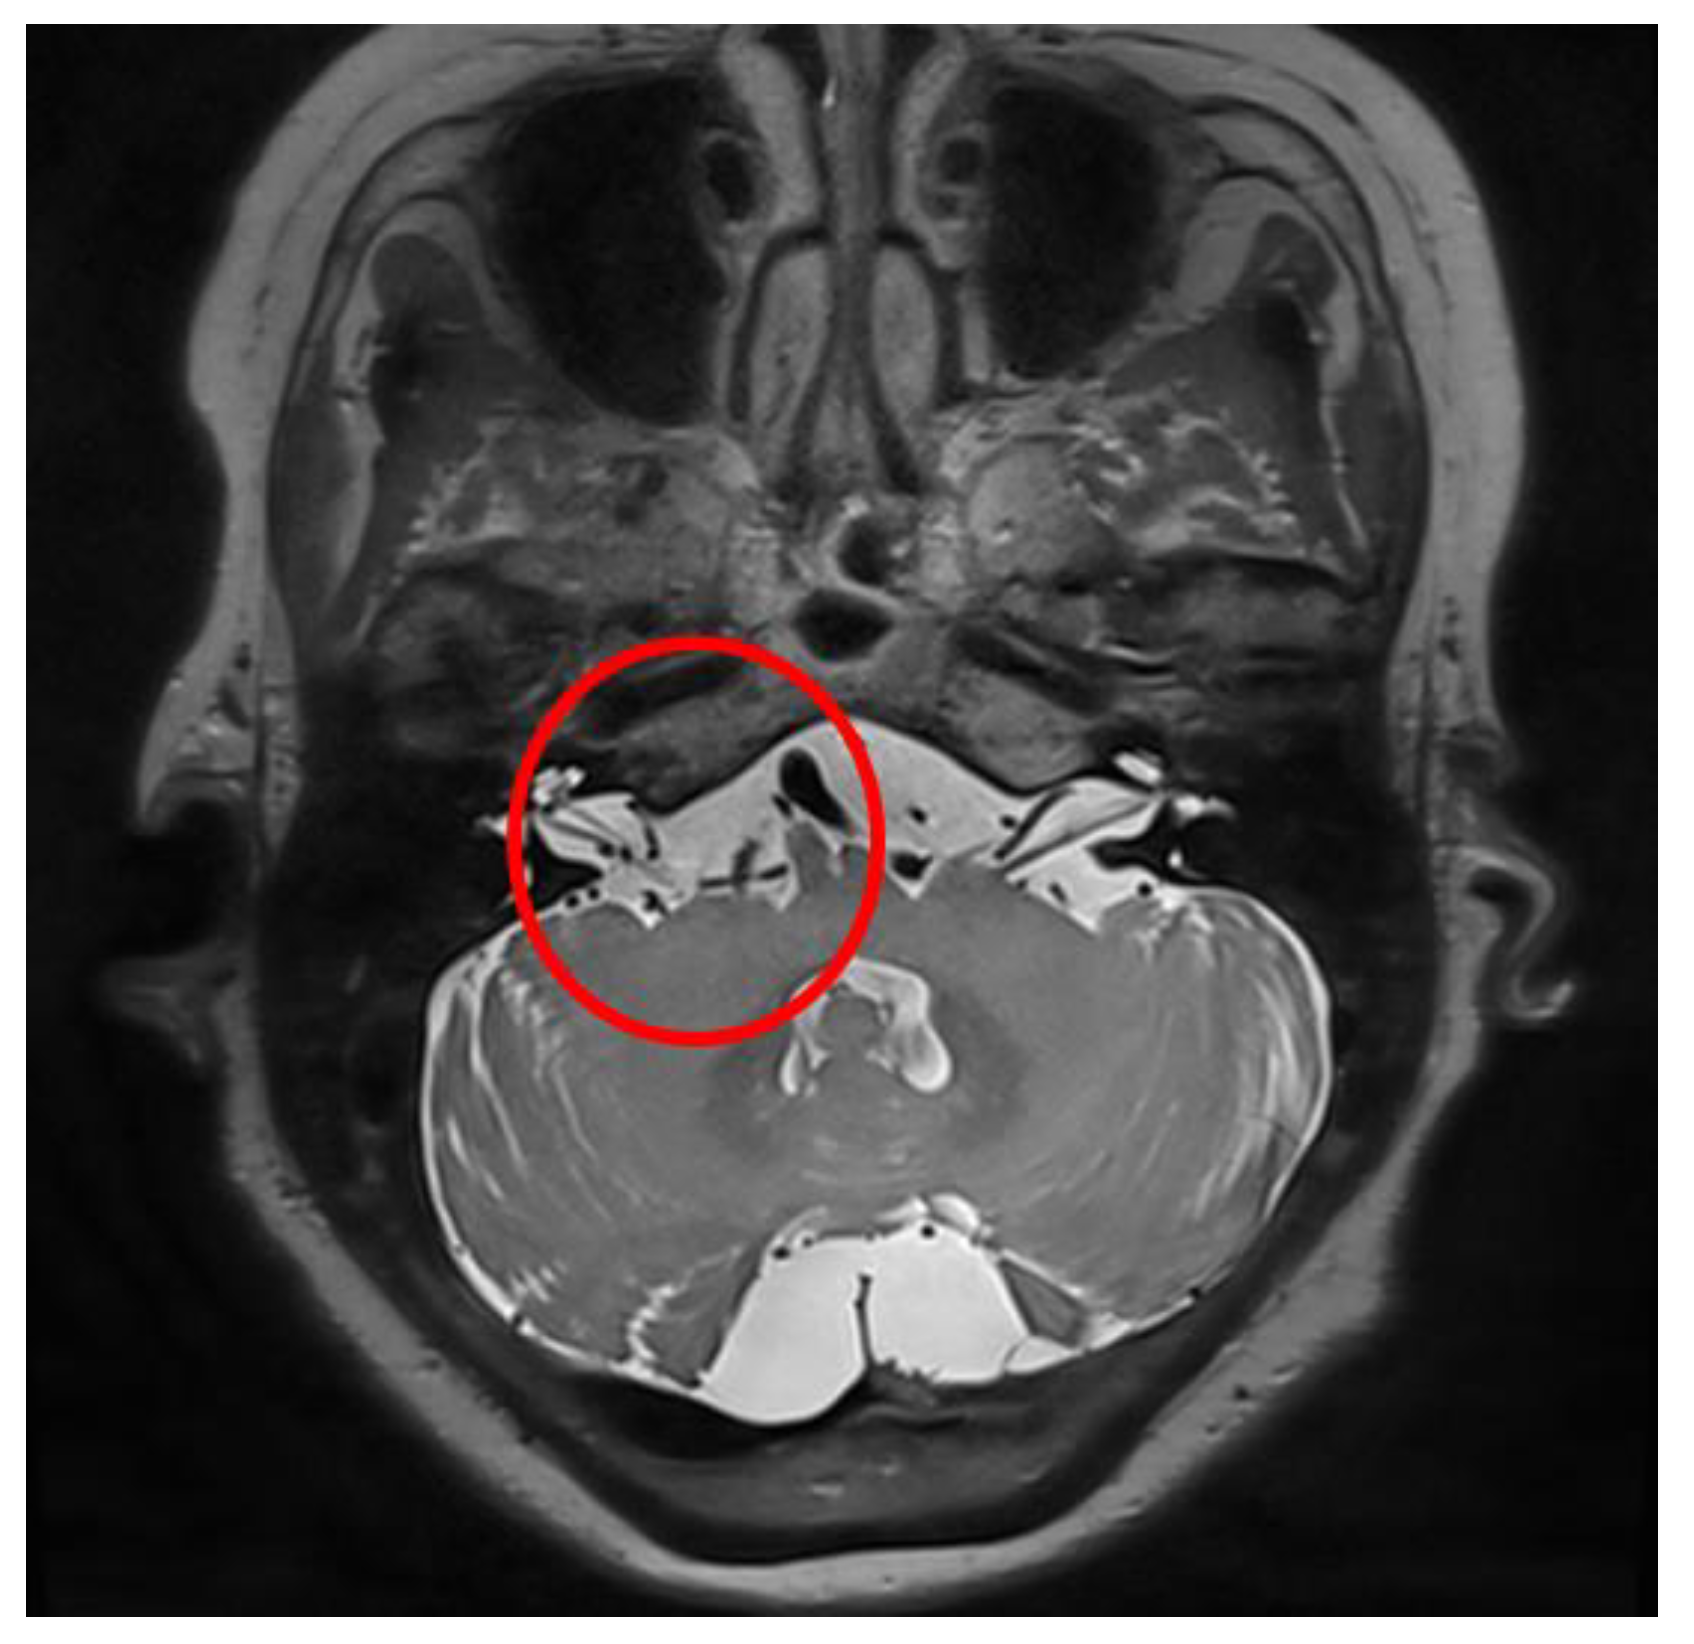

Illustrative Case